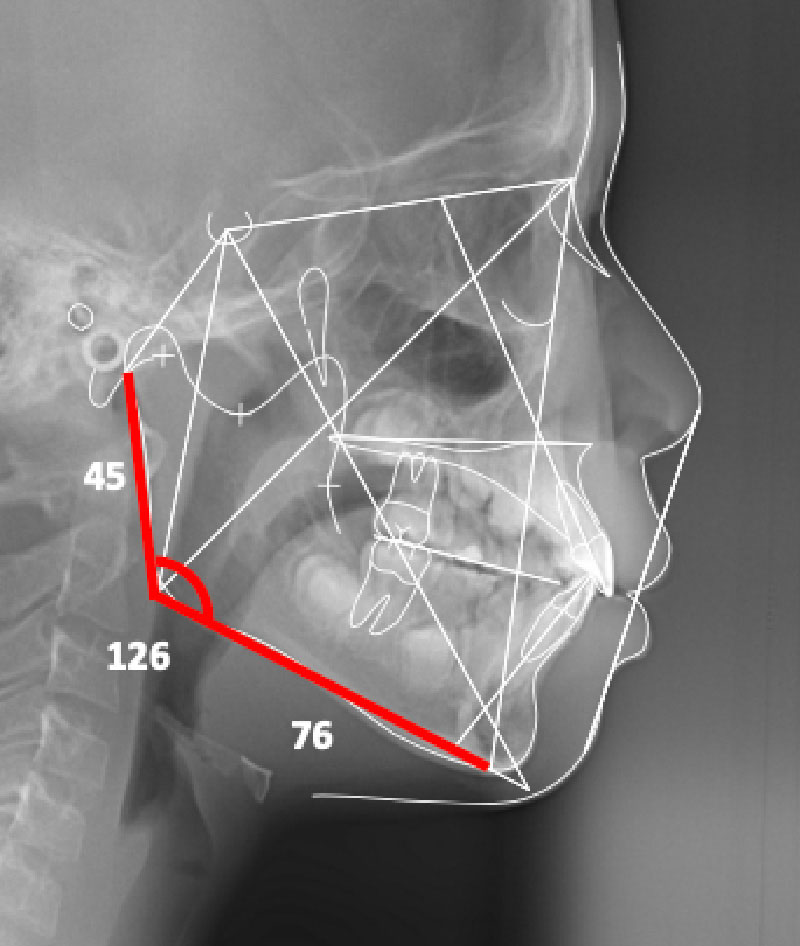

スプリント後頭部X線規格写真

頭部X線規格写真

約2年間で下顎は大きく成長しました。下顎の前方への成長と共に気道(エアウェイ)も広がっています。将来、睡眠時無呼吸症候群の発生を防ぐことになります。

治療前

スプリント後

矯正治療後頭部X線規格写真

スプリント治療後(=矯正治療開始時)には、下顎は大きく成長しました。下顎の前方への成長と共に気道(エアウェイ)も広がっています。矯正治療中にもさらに下顎は成長、矯正治療のメカニクスで下顎を反時計回転させ、その結果オトガイが前方に出て、顔立ちに大きく影響しています。小臼歯の抜歯(歯を並べるためにも必要でした)が顔の印象の改善に大きく関わっています。